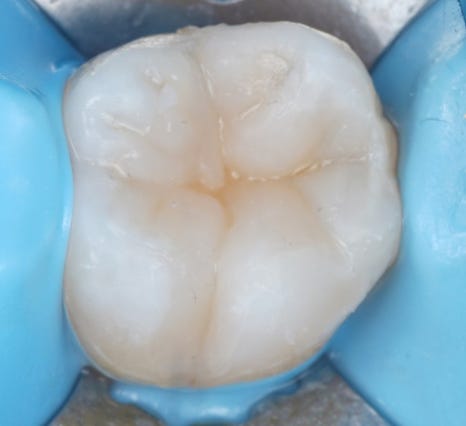

충치를 모두 제거한 뒤, 큐레이로 또 확인해 봤습니다.

촬영일 : 251201

이제 붉은빛이 거의 사라졌죠? 아주 조금 남은 부위도 깨끗하게 제거했습니다.

다음으로는 표면처리를 하여 기계적으로 고정될 수 있게 만든 다음, 접착제를 이용하여 레진이 잘 붙을 수 있도록 했어요.

마지막으로 레진으로 치아 형태를 하나하나 만들어갔어요.

해당 치아와 닿는 위쪽 어금니와 해당 치아의 반대쪽 어금니의 형태를 참고하여 실제 환자분의 치아의 형태를 그대로 재현하도록 했습니다.

한 번에 쭉 채워 넣는 방식이 아니라

조금씩 채워 넣으면서

쌓아가는 과정입니다.